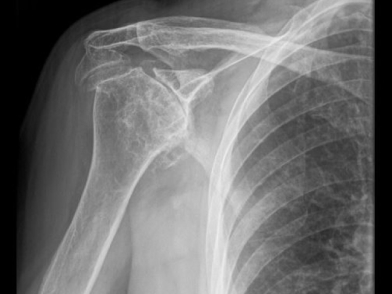

Η επιλογή μεταξύ των προαναφερθεισών τύπων προθέσεων εξαρτάται κυρίως από τη βιολογική ηλικία του ασθενούς, την κατάσταση των μυών του στροφικού πετάλου και την ακεραιότητα των τενόντων τους, καθώς και την ακριβή ένδειξη για την αρθροπλαστική ώμου. Η ανατομική ολική αρθροπλαστική ώμου ενδείκνυται γενικότερα για την πρωτοπαθή και τη δευτεροπαθή οστεοαρθρίτιδα του ώμου, υπό την προϋπόθεση ότι υπάρχει επαρκές οστικό υπόβαθρο στην ωμογλήνη, ότι οι μυς του στροφικού πετάλου και ο δελτοειδής είναι ακέραιοι και λειτουργικοί, ότι το βραχιόνιο πλέγμα (το μείζον νευρικό πλέγμα που νευρώνει το άνω άκρο) είναι πλήρως λειτουργικό, ότι δεν υπάρχει προς τα άνω μετατόπιση της βραχιονίου κεφαλής γεγονός που θα υποδείκνυε την παρουσία αρθροπάθειας του στροφικού πετάλου, καθώς και ότι δεν υπάρχει κάποια ένδειξη ενεργού λοίμωξης. Η ημιαρθροπλαστική του ώμου από την άλλη πλευρά, ενδείκνυται είτε σε περιπτώσεις πρωτοπαθούς αρθρίτιδας όπου το στροφικό πέταλο είναι ανεπαρκές ή το οστικό υπόβαθρο της ωμογλήνης υπολείπεται, είτε σε νεότερους ασθενείς και χειρώνακτες εν ενέργεια, λόγω της αυξημένης πιθανότητας χαλάρωσης της πρόθεσης της ωμογλήνης σε αυτές τις ηλικιακές ομάδες. Ενδείκνυται επίσης σε επιλεγμένες περιπτώσεις αρθροπάθειας του στροφικού πετάλου, στην οστεονέκρωση της βραχιονίου κεφαλής χωρίς συμμετοχή της ωμογλήνης, σε ορισμένα 3 τεμαχίων και στα περισσότερα 4 τεμαχίων κατάγματα εγγύς βραχιονίου, και σχεδόν σε όλα τα ενδαρθρικά κατάγματα της βραχιονίου κεφαλής σε ασθενείς νεότερους από 65 έως 70 ετών. Τέλος, η ανάστροφη πρόθεση ενδείκνυται σε πιο ηλικιωμένους ασθενείς με αρθροπάθεια του στροφικού πετάλου, στην οστεοαρθρίτιδα του ώμου με συνοδό, μη επιδιορθώσιμη ρήξη του στροφικού πετάλου, στα τριών και τεσσάρων τεμαχίων κατάγματα εγγύς βραχιονίου καθώς και στα ενδαρθρικά κατάγματα της βραχιονίου κεφαλής σε ασθενείς μεγαλύτερους από 70 ετών ή με σοβαρή οστεοπενία, στη ρευματοειδή αρθρίτιδα του ώμου, υπό την προϋπόθεση ότι υπάρχει επαρκές οστικό υπόβαθρο στην ωμογλήνη και, τέλος, μετά από αποτυχημένη ημιαρθροπλαστική ή ανατομική αρθροπλαστική ώμου. Σημειωτέον ότι για να είναι επιτυχημένη η ανάστροφη αρθροπλαστική ώμου είναι επιτακτικής σημασίας να είναι ακέραιος και λειτουργικός ο δελτοειδής μυς.

Όσον αφορά τις επιπλοκές της αρθροπλαστικής ώμου, αυτές μπορούν να κατηγοριοποιηθούν, πρώτον, σε γενικές, οι οποίες μπορεί να περιλαμβάνουν τη λοίμωξη, την εν τω βάθει φλεβοθρόμβωση, την κάκωση σε γειτονικά αγγεία και νεύρα, τη δυσκαμψία της άρθρωσης και το μειωμένο εύρος κίνησης, την άσηπτη χαλάρωση του βραχιονίου προθέματος, την αποτυχία της συρραφής/αποκατάστασης του τένοντα του υποπλατίου και τη συνακόλουθη πρόσθια αστάθεια της άρθρωσης (πρόσθιο εξάρθρημα), τη πώρωση ή την πώρωση σε πλημμελή θέση των βραχιονίων ογκωμάτων και το περιπροθετικό κάταγμα (διεγχειρητικό ή μετεγχειρητικό). Δεύτερον, υπάρχουν οι επιπλοκές που αφορούν ειδικά κάθε παραλλαγή της αρθροπλαστικής ώμου, όπως η χαλάρωση της πρόθεσης της ωμογλήνης στην TSA, η χαλάρωση της ωμογλήνης, η δημιουργία εγκοπής (notching) στην ωμογλήνη ή το κάταγμα ανεπαρκείας του ακρωμίου στην RSA και η πρόσθια-άνω διαφυγή της πρόθεσης στην ΗΑ. Παρ’ ότι ο κατάλογος μπορεί να φαίνεται μακρύς, η πλειοψηφία αυτών των επιπλοκών θεωρούνται ασυνήθεις, ενώ πολλαπλά είναι τα μέτρα που λαμβάνονται για την αποφυγή τους ή έστω την έγκαιρη διάγνωση και αντιμετώπισή τους σε κάθε βήμα της χειρουργικής επέμβασης και της μετεγχειρητικής πορείας.